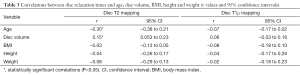

Table 1 shows the values of relaxometry for each lumbar disc. The cranial and caudal segments of the lumbar spine, namely L1L2 and L5S1, respectively, had the lowest relaxation time values, while the highest values were observed for the L3L4 central disc segments. A similar trend was observed for the IVD volumes. The average relaxation times for men were T2 =116.0±15.9 ms and T1ρ =51.6±9.1 ms; for women, T2 =114.7±13.7 ms and T1ρ =52.9±12.2 ms. There was no significant difference between men and women for either relaxometry map (T2, P=0.37; T1ρ, P=0.97). The relaxation times of the NP were higher than the anterior and PAF both T2 (Kruskal-Wallis =37.37; P<0.0001) and T1ρ (Kruskal-Wallis =45.49; P<0.0001). In T2 relaxometry there was no difference between the anterior and posterior annulus, however, in the AAF T1ρ relaxometry values were higher than the PAF (Table 2).

Figure 4 shows a graphical representation of the relationship between the relaxation times obtained by relaxometry maps and the subject characteristics. There was a negative correlation between age and T2 relaxation time (r=−0.30, P<0.0001) and a positive correlation between disc volume and relaxation time T2 (r=0.15, P=0.002) (Table 3).

As shown in Table 4, we observed a negative linear correlation between T2 relaxation times and age at all lumbar disc levels (P<0.02 at all levels). There was no correlation between age and volumetry for any disc (P>0.07 at all levels). We also observed no relationship between age and T1ρ values for any disc level (P>0.06 at all levels). BMI, height and weight were not correlated with any lumbar IVD relaxometry measurement.

The stratification of the IVD into NP, AAF and AAF made possible to analyze separately the correlation of each sub-region with ageing (Figure 6). Table 2 shows the correlation values (r) for each disc sub-region (NP, and PAF AAF) at each disc level (L1L2 to L5S1). T2 relaxation times of NP and PAF correlate negatively with aging at all disc levels, except for the sub-region PAF in L5S1 disc. T1ρ relaxometry correlates only with the sub-region NP of L1L2 and L3L4 IVDs.